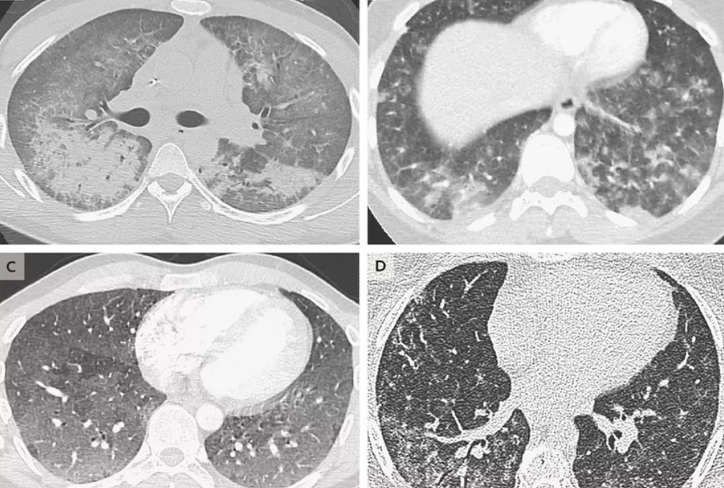

Vaping products like cannabis have chemical called vitamin E acetate which was the main source of the mystery disease that has killed 6 people by far and has made almost 500 people sick.

Patients suffering from the disease suffer from shortness of breath, nausea, vomiting, fever, and cough.